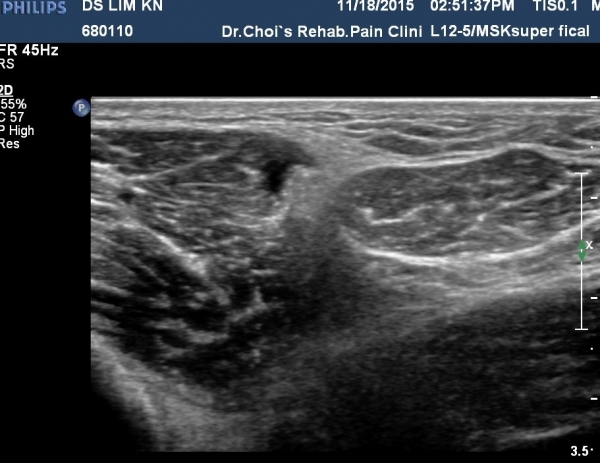

¹«¸­ ¿ÜÃø Á¾´Ü¸é°Ë»ç¿¡¼­ °üÀý³» ¼ö¾×Àú·ù°¡ °üÂûµÊ(»çÁø 1, 2).

¹«¸­À§  ³»Ãø sartorius Ⱦ´Ü¸é°Ë»ç¿¡¼­ sartorius¿Í ³»Ãø ±¤±Ù »çÀÌ¿¡¼­ saphenous ½Å°æÀÇ ½½°üÀý ºÐÁö°¡ °üÂûµÊ(»çÁø 3).